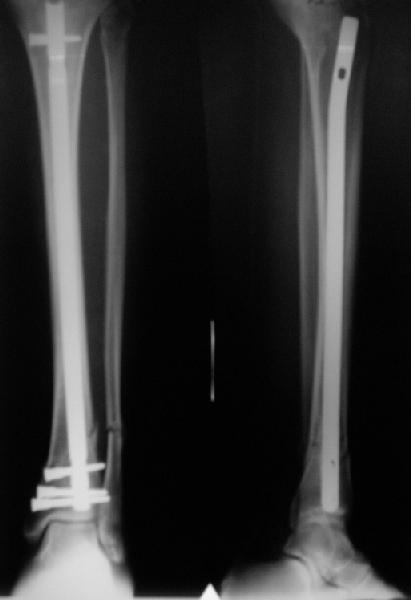

In delayed cases acute length restoration performed only in the tibia may leave the fibula shortened thus change the mortise. So it is reasonable to restore length of both bones simultaneously by distractor and fix the fibula not with open reduction and plating but just by a single perQ screw. Example attached.

I am just trying to illustrate that prevention of 1)tibial valgus and 2)loss of reduction can be provided without fibular plating. Small changes of conventional nailing techniques allow to maintain reduction of the tibia reliably without adjunctive fibular stabilization.